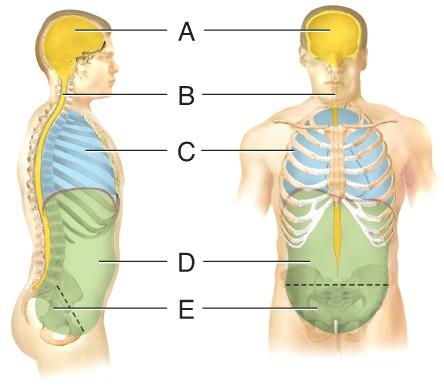

Name the cavity A.

dorsal

cranial

vertebral

ventral

cranial

Name the cavity C.

cranial

thoracic

abdominal

pelvic

thoracic

Name the cavity formed by A and B.

abdominopelvic

ventral

dorsal

pelvic

dorsal

Name the cavity formed by D and E.

ventral

abdominopelvic

dorsal

thoracic

abdominopelvic

Name the cavity formed by C, D and E.

dorsal

cranial

ventral

abdominopelvic

ventral

Name the cavity E.

cranial

pelvic

abdominal

thoracic

pelvic